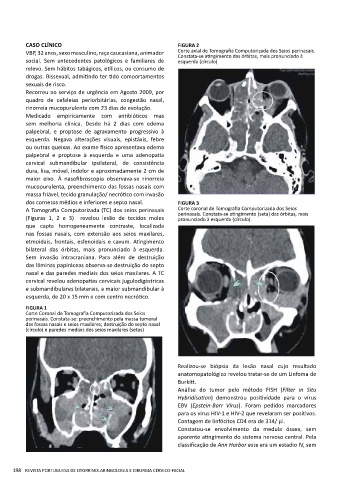

CASO CLÍNICO FIGURA 2

VBP, 32 anos, sexo masculino, raça caucasiana, animador Corte axial de Tomografia Computorizada dos Seios perinasais.

Constata-se atingimento das órbitas, mais pronunciado à

social. Sem antecedentes patológicos e familiares de esquerda (círculo)

A Tomografia Computorizada (TC) dos seios perinasais Corte coronal de Tomografia Computorizada dos Seios

perinasais. Constata-se atingimento (seta) das órbitas, mais

(Figuras 1, 2 e 3) revelou lesão de tecidos moles pronunciado à esquerda (círculo).

que capta homogeneamente contraste, localizada

nas fossas nasais, com extensão aos seios maxilares,

etmoidais, frontais, esfenoidais e cavum. Atingimento

bilateral das órbitas, mais pronunciado à esquerda.

Sem invasão intracraniana. Para além de destruição

das lâminas papiráceas observa-se destruição do septo

nasal e das paredes mediais dos seios maxilares. A TC